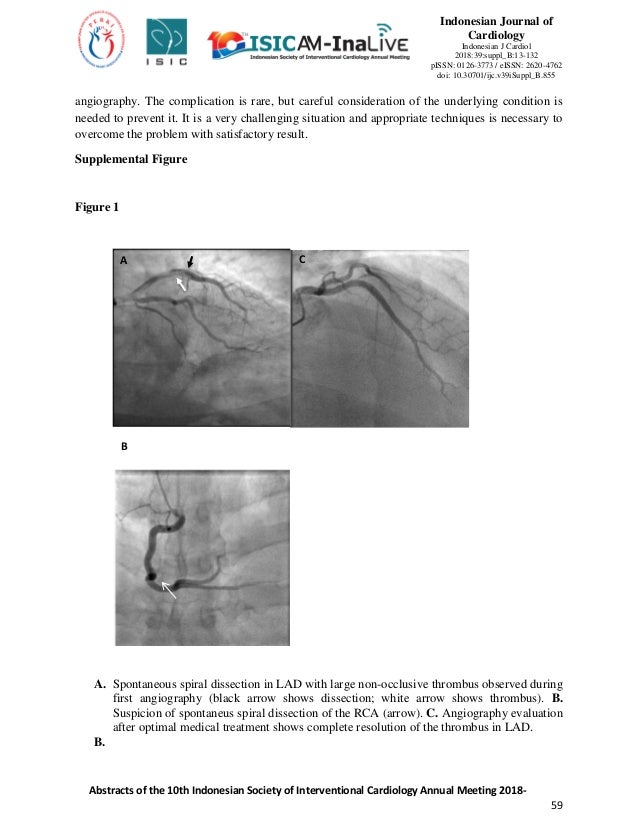

Abstracts Of The 10th Indonesian Society Of Interventional Cardiology